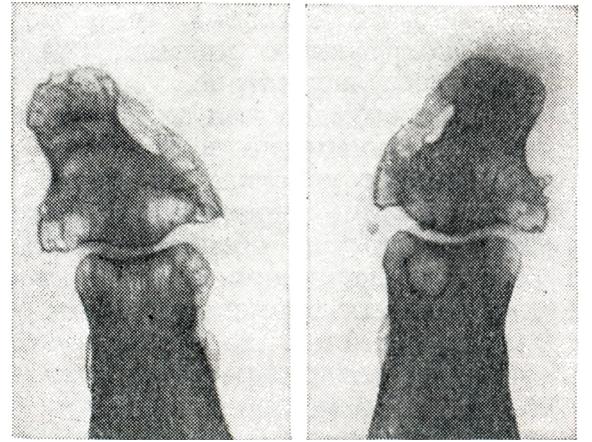

Рис. 1. | ||

В синовиальной оболочке наряду с гиперемией и отеком микроскопически обнаруживают пролиферацию и десквамацию покровных синовиоцитов, гипертрофию ворсин (рис. 1), пленки фибрина на поверхности, очаги фибриноидного набухания, диффузные инфильтраты, преимущественно из лимфо-гистиоцитарных элементов и единичных плазматических клеток. Наблюдается также разволокнение и фибриноидное набухание стенок мелких артерий и вен не только синовиальной оболочки, но и капсулы сустава и периартикулярных тканей. В воспалительный процесс вовлекаются нервы и чувствительные нервные окончания, что обусловливает резкую болезненность сустава. Суставной хрящ микроскопически не изменен. Может быть остеопороз эпифизарных отделов костей.